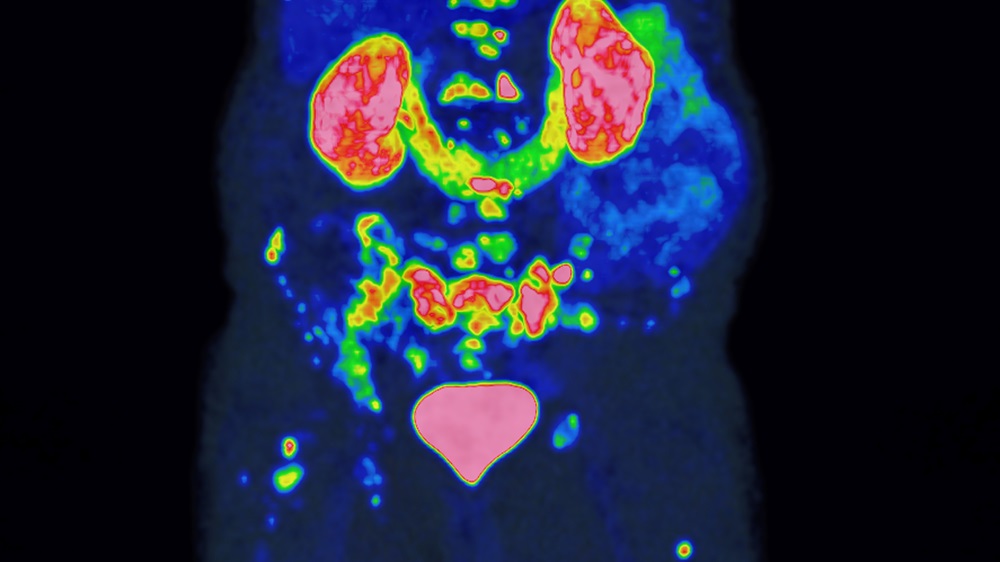

Der Preis der Deutschen Hochschulmedizin 2025 geht an die internationale Initiative PROMISE. Das Forschungsteam unter Federführung der Universitätsmedizin Essen entwickelte eine Methode, um mit hochgenauer Bildgebung den Verlauf von Prostatakrebs noch präziser vorherzusagen und Therapien individueller zu steuern. Das Projekt ist ein herausragendes Beispiel für eine internationale und interdisziplinäre Zusammenarbeit, die Forschungsergebnisse in Rekordzeit in die klinische Anwendung überführt.

Das PROMISE-Team nutzte für die Risikobewertung die PSMA-PET. Ein hochmodernes Bildgebungsverfahren, mit dem sich Prostatakrebszellen besonders präzise und ihr Ausbreitungsstadium im Körper sichtbar machen lassen. Da die Methode empfindlicher ist als ältere Verfahren, mussten ihre Befunde zunächst in neue Behandlungsempfehlungen übersetzt werden. Ein Prozess, den PROMISE maßgeblich geprägt hat. In einer der größten Studien weltweit wertete das Team Bilddaten von über 15.000 Patienten aus. Gemeinsam mit international führenden Forschungseinrichtungen entwickelte es daraus das PROMISE-Schema. Eine Methode, mit der sich individuelle Risikoprofile auf Basis der PSMA-PET deutlich präziser bestimmen lassen. Darauf aufbauend entstanden Nomogramme, also Vorhersagemodelle für das individuelle Risiko, die für Ärzt:innen und Patient:innen verständlich aufbereitet und zur gemeinsamen Therapieentscheidung nutzbar sind.